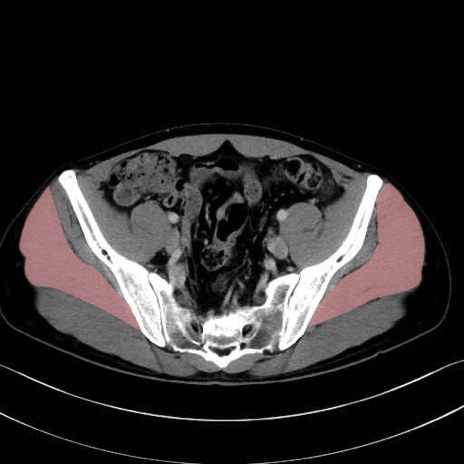

腸骨筋 (Iliacus)

3. 殿部の筋肉(表層・中層・深層)

大殿筋 (Gluteus maximus)